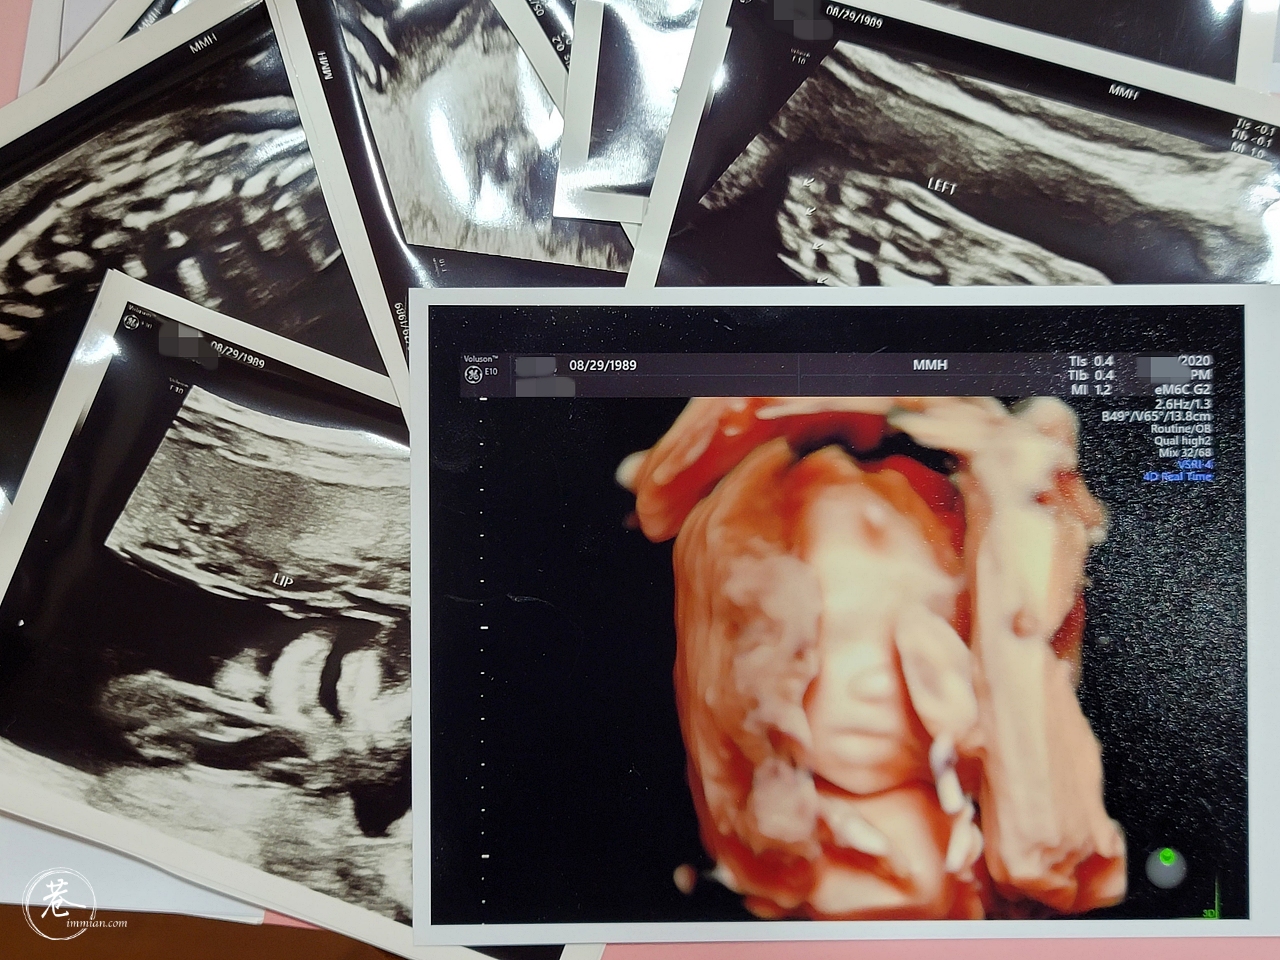

▲每次產檢後醫院會印幾張超音波照給我,然後我就會寫上註解傳給老公跟家人,這些小記錄是每週的小確幸。